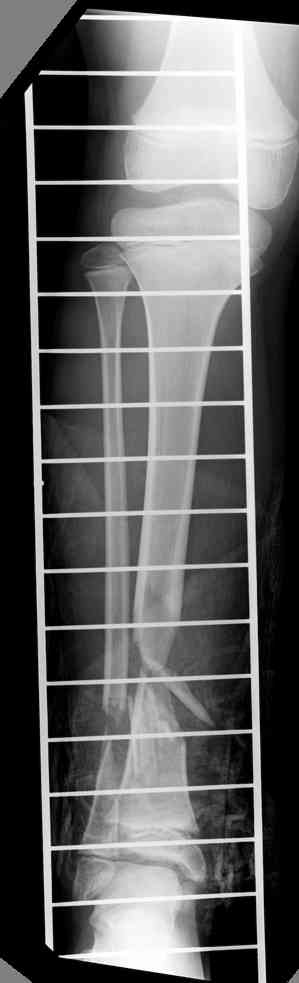

-->> дистальный фрагмент слишком короткий, меньше 2 см, нет места для интрамедуллярного штифта, в отличии от пациента Др. Иванова (прекрастный результат!).

Another choice is simply perform shortening + posterior angulation with Ilizarov or TSF , than gradual correction of the angulation.After all apply third ring on the proximal tibia and start lengthening.

We had recently similar case in 14 years old boy with 45 mm bone defect after open tibial fracture.Boy doing excellent .This technique is not new, Sasha Lerner did it in Rambam , Rozbruch wrote also.

Действительно, если есть длинная косая линия на проксимальном отломке, это жалко будет не использовать. Можно сделать коррекцию угла не обратным разведением фрагментов, а оставить их в контакте, и сделать кортикотомию проксимальнее на 2-3 см. Можно и сейчас отсечь такой фрагмент и транспортировать его с разворотом. Наверно, вариант с ангуляцией более технологичен.

Да, надо удалить все железо, сделать для ангуляции остеотомию малоберцовой на уровне дефеормации, а после восстановления оси сразу освободить стопу. То есть в дистальном отломке tibia надо побольше

спиц с упорами, а на диафизе только half-pins с передне-внутренней стороны, чтобы как можно меньше пострадала передняя группа мышц.